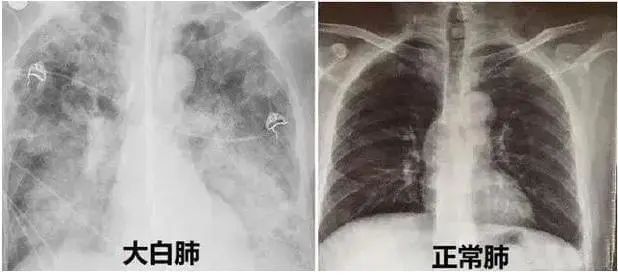

近期,多地醫(yī)生發(fā)現(xiàn)患者出現(xiàn)肺炎或白肺癥狀,引發(fā)關(guān)注。那么什么是白肺呢?其實白肺是肺部影像學(xué)表現(xiàn)的一個口語化描述。當(dāng)出現(xiàn)炎癥和感染,肺泡被滲出液等填充,在影像學(xué)上的表現(xiàn)就是出現(xiàn)白色區(qū)域。并不是只要肺部出現(xiàn)了炎癥就都叫白肺,一般來講肺部炎癥較重、滲出液較多,白色的影像區(qū)域面積達(dá)到70%?80%時,在臨床上把它稱為白肺。通過“啄醫(yī)生”可以準(zhǔn)確地識別新冠肺炎的典型白肺影像,以下選取幾例最新病例加以說明。

胸片顯示整個雙肺已經(jīng)白化